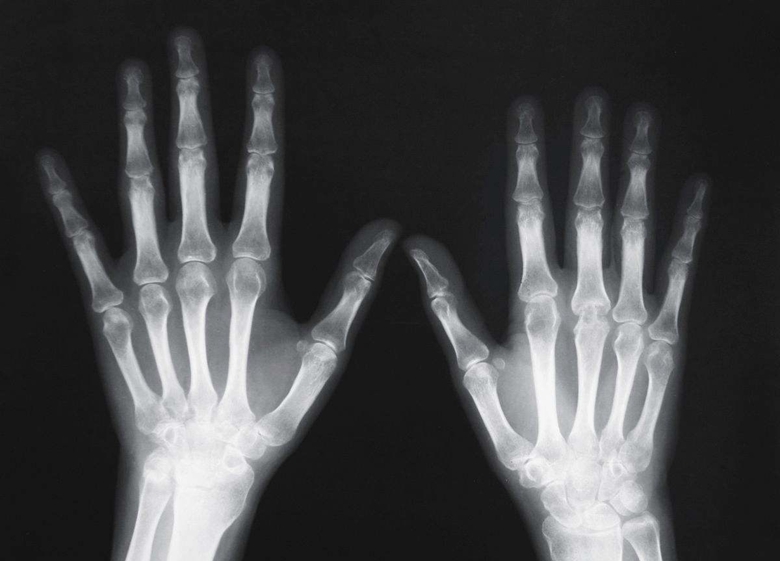

X線檢查作為輔助檢查方法之一。臨床醫(yī)學(xué)上常用的X線檢查方法有透視和攝片兩種。

攝片能使受檢部位結(jié)構(gòu)清晰地顯示于X線片上,并可作為客觀記錄長(zhǎng)期保存,以便在需要時(shí)隨時(shí)加以研究或在復(fù)查時(shí)作比較。必要時(shí)還可作X線特殊檢查,如斷層攝影、記波攝影以及造影檢查等。選擇何種X線檢查方法,必須根據(jù)受檢查的具體情況,從解決疾?。ㄓ绕涫枪强萍膊。┑囊蠛团R床需要而定。X線檢查僅是臨床醫(yī)學(xué)輔助診斷方法之一。